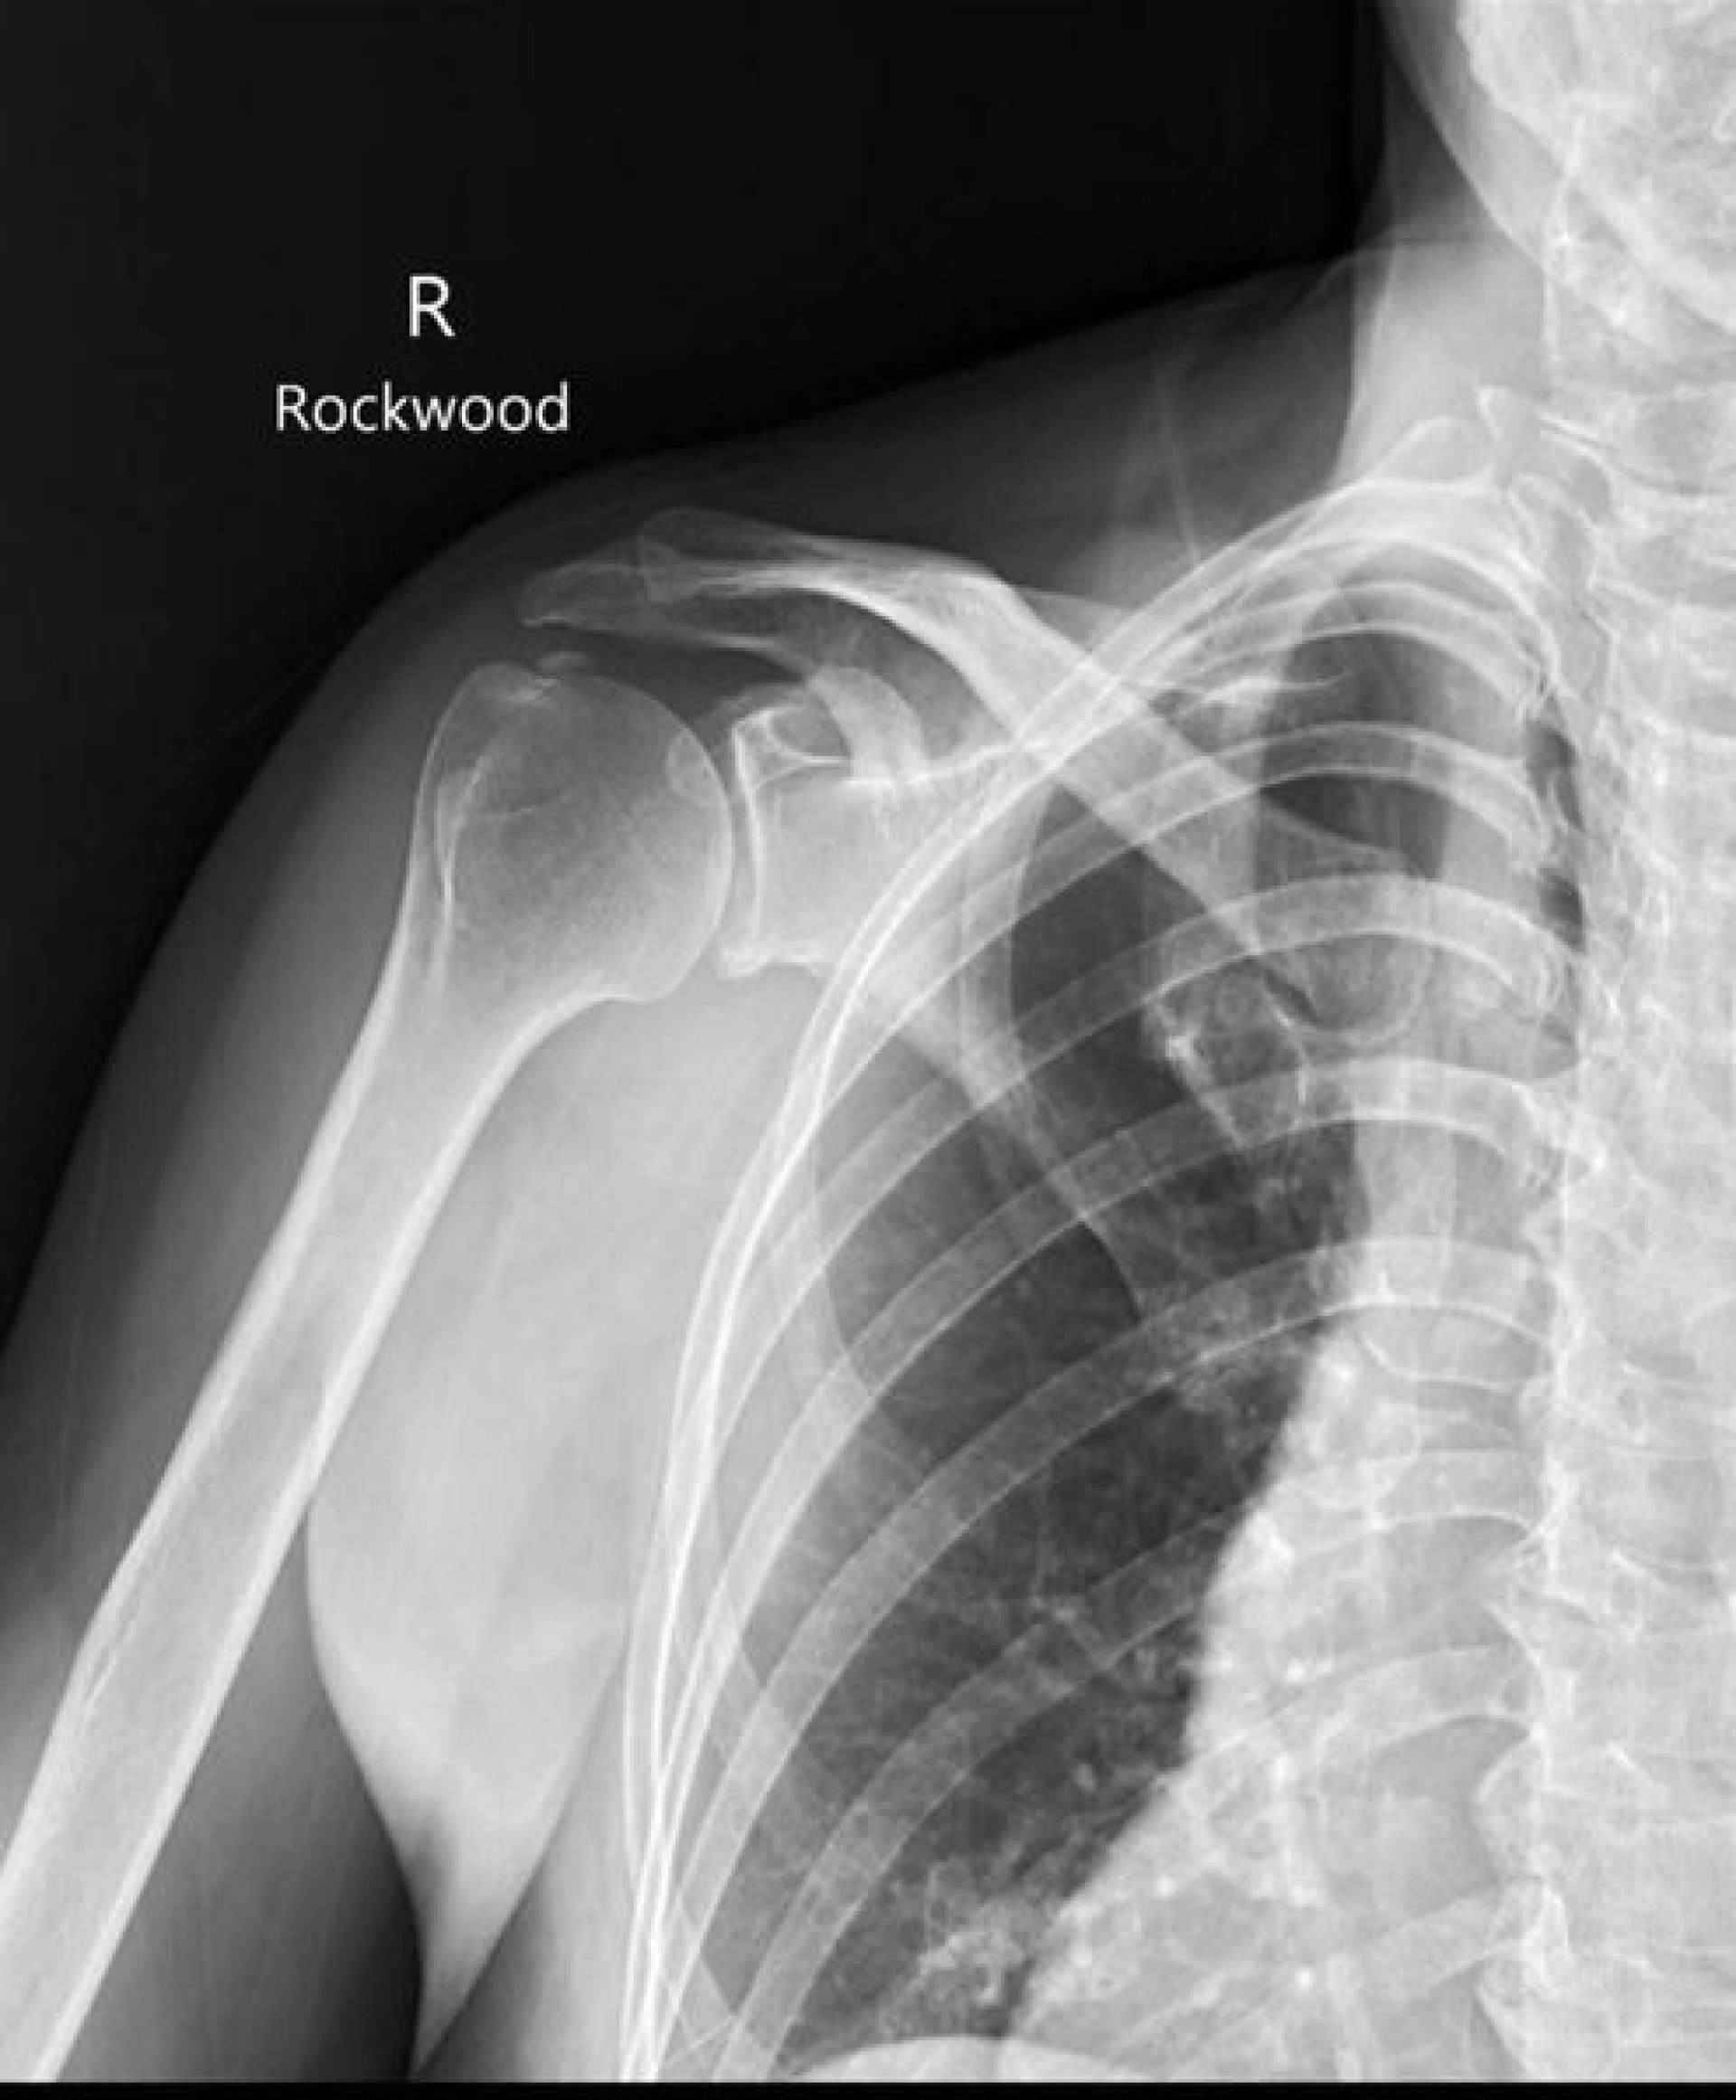

เป็นอาการไหล่ติดเนื่องจาก หินปูน ที่เอ็นกล้ามเนื้อหัวไหล่ ร่วมกับเอ็นหัวไหล่อักเสบ และมีการเยื่อหุ้มหัวไหล่ติดตึงครับ (Calcific Tendinitis)

โดยเคสนี้ช่วงแรกส่งมาทำกายภาพ เพื่อเพิ่มองศาการเคลื่อนไหวหัวไหล่ และลดปวด ซึ่งการรักษาทางกายภาพบำบัดเป็นไปได้ยากมาก ไม่ว่าจะลองทำ Shockwave Laser Ultrasound และ ดัดข้อต่อ (Mobilization) ไม่สามารถลดปวดและเพิ่มองศาการเคลื่อนไหวได้เลย

จึงส่งกลับไปปรึกษาแพทย์เพิ่มเติม โดยแพทย์ก็แนะนำให้ทำการผ่าตัด เพื่อนำหินปูนออก (Calcification Remove) หลังจาการผ่าตัดก็ส่งทำกายภาพต่อ ซึ่งส่งผลค่อนข้างดี สามารถลดปวดและเพิ่มองศาการเคลื่อนไหวได้ง่ายขึ้น ซึ่งเคสนนี้ใช้เวลารักษารวมค่อนข้างนาน โดยรวมใช้เวลาประมาณ เกือบ 1ปี ซึ่งปัจจุบันคนไข้สามารถกลับมาใช้หัวไหล่ได้เกือบปกติ ไม่มีอาการปวด แต่ยังขาดความแข็งแรงของกล้ามเนื้อสะบัก และหัวไหล่อยู่ จึงนัดทำกายภาพบำบัดสัปดาห์ละ1ครั้ง เพื่อปรับเปลี่ยน โปรแกรมออกกำลังกายและลดอาการติดๆจากการใช้งาน